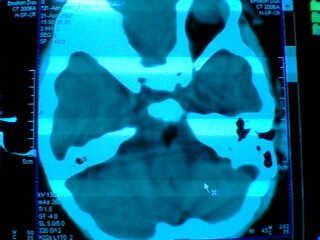

发热2天 无咳嗽咳痰 抽搐数次 现浅昏迷

其它层面无异常表现 故未上传

脂肪瘤?皮样囊肿?表皮样囊肿?

考虑 脑干脂肪瘤可能性大

位于中线部位,多考虑脂肪瘤

基底池脂肪瘤。

考虑:左侧桥小脑角池、基底池表皮样囊肿可能性大。